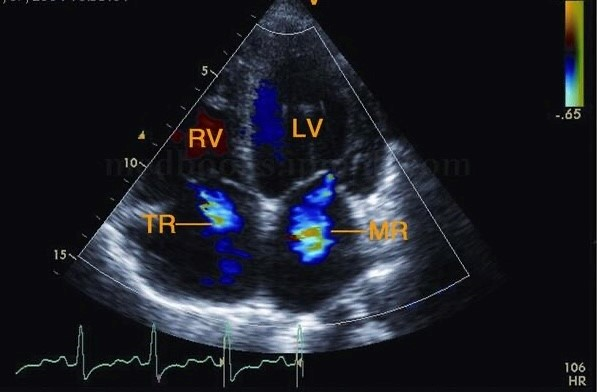

二、瓣膜形态、房室大小功能正常的房室瓣反流

世界上没有透风的墙,也就允许存在微量和少量反流的房室瓣存在。对于瓣膜形态、房室大小及功能正常的房室瓣反流,无须大惊小怪。不放心的可以一年左右复查一次心脏超声。